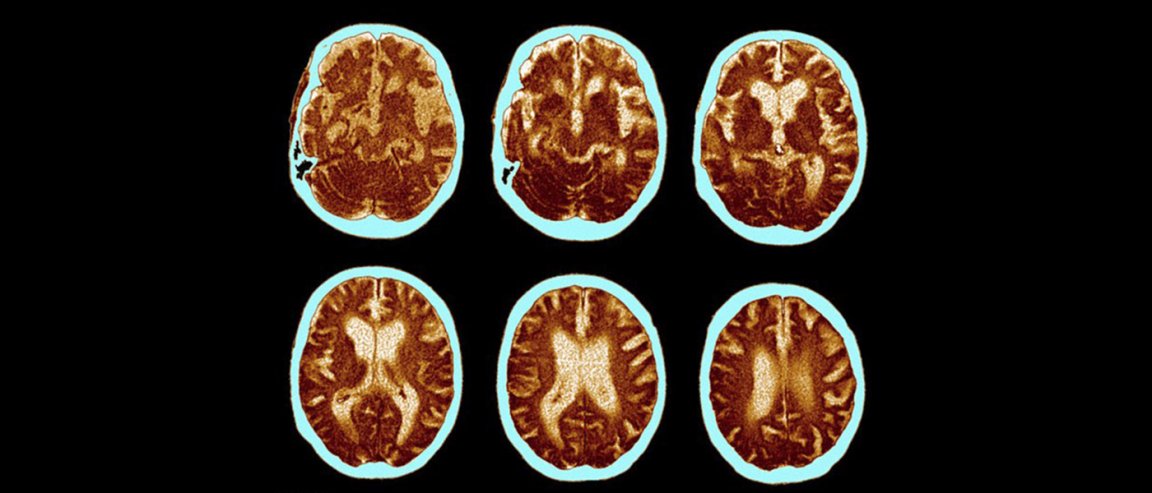

The drug, described in the journal Nature, is called aducanumab, and it targets the toxic amyloid beta plaque, which are tangled clumps of protein that formed in the brains of patients with Alzheimer’s. According to the researchers, the “human monoclonal antibody” prompts the immune system to selectively target and clear the aggregated plaques, which, in turn, could slow down the disease.

Pharmaceutical company Biogen, which funded the trial, said the antibody has been tested in both animal models and a small group of 165 patients with prodomal and mild Alzheimer’s disease. After a year of study, the researchers found that virtually all the amyloid plaques appeared to have gone in patients that were given the highest doses of the drug.